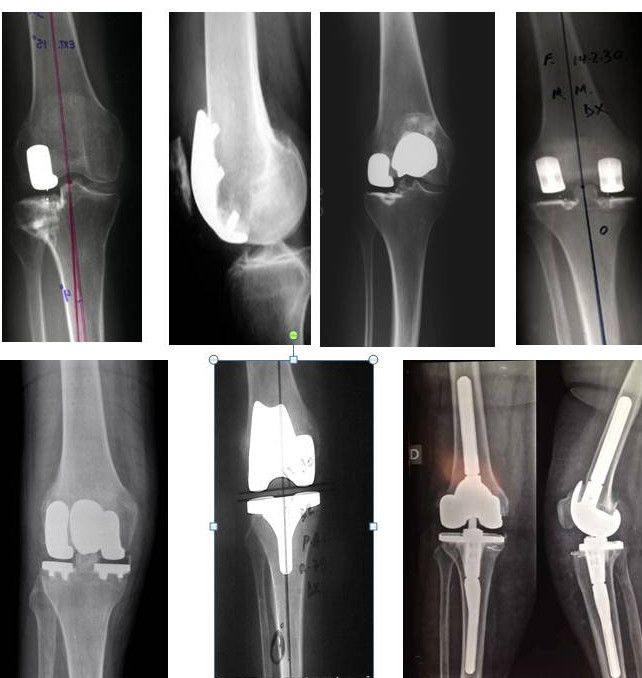

Protesi ginocchio

Ginocchio

Questo tipo di protesi è utilizzato per il trattamento di forme non gravi di gonartrosi. Nei centri con le maggiori casistiche del settore rappresentano mediamente il 20 per cento del numero totale di protesi di ginocchio eseguite...